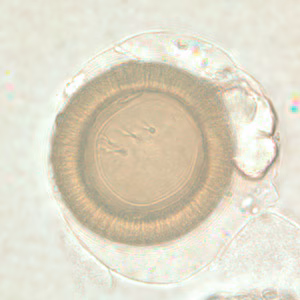

Taenia spp. eggs.

Microscopic identification of eggs and proglottids in feces is diagnostic for taeniasis, but is not possible during the first 3 months following infection, prior to development of adult tapeworms. Repeated examination and concentration techniques will increase the likelihood of detecting light infections. Nevertheless, identification of Taenia is not possible if solely based on microscopic examination of eggs, because all Taenia species produce eggs that are morphologically identical. Eggs of Taenia spp. are also indistinguishable from those produced by cestodes of the genus Echinococcus (tapeworms of dogs and other canid hosts). Microscopic identification of gravid proglottids (or, more rarely, examination of the scolex) allows species determination.